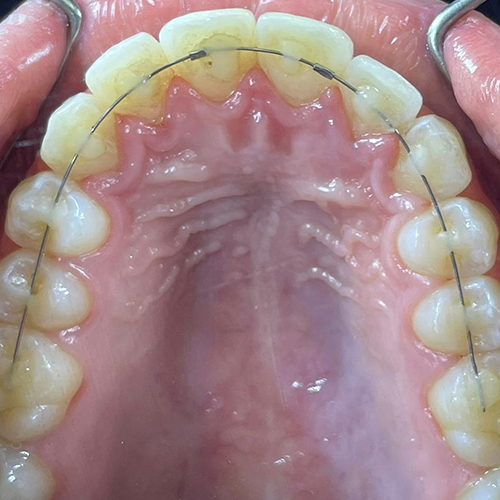

Comprueba en la práctica cómo el conocimiento se transforma en resultados reales a través de los casos de nuestros alumnos.

SALA DE PROCEDIMIENTOS

Siga clases prácticas y la evolución de casos clínicos reales directamente desde la clínica del Dr. Ary Nunes.